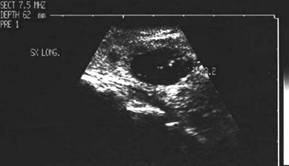

Femeie de 70 ani. Disfonie progresiva prin

paralizie de recurent drept. Nodul voluminos (35 x 25 x 43 mm, 19 cc) care ocupa

aproape complet lobul drept, neomogen, hipoecogen, cu arie anterioara

hipoecogena. Lob stang nevizuzlizat (probabil agenezie). Calcitonina =

820 pg/ml. (v.n. <10pg)

CEA= 638 ng/ml (v.n. <8 ng).

Examen citologic prin citoaspiratie: carcinom midolar cu celule spindle.

CT – aceeasi pacienta – agenezie lob stang